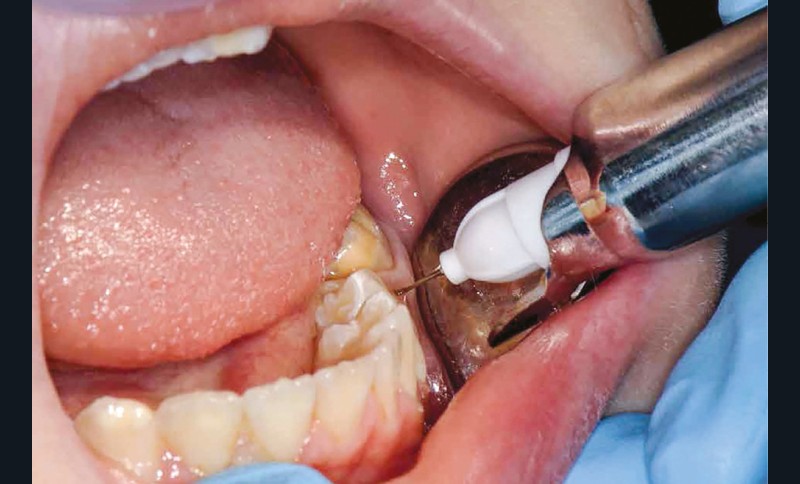

Parmi les techniques d’anesthésie qui s’offrent à nous, l’anesthésie ostéocentrale apparaît comme fiable, facile à mettre en place, immédiate et bien acceptée chez l’enfant [4-6].

Afin d’optimiser les séances de soins, l’anesthésie intra-osseuse par injection électronique a été réalisée avec le Quicksleeper 5® dans les deux secteurs (fig. 3 et 4) afin de permettre la réalisation des coiffes préformées métalliques sur 36 et 46 dans la même séance (fig. 5 à 7). Il aurait été difficilement envisageable de réaliser les coiffes dans la même séance en utilisant une anesthésie tronculaire dans chaque secteur.

L’évolution de la médecine bucco-dentaire permet d’envisager des traitements efficaces. À l’heure actuelle, l’anesthésie ostéocentrale, notamment avec la réalisation d’injection assistée électroniquement grâce au Quicksleeper 5®, représente un outil incontournable (rapide, efficace, sécurisant) dans la prise en charge des patients en odontologie pédiatrique.